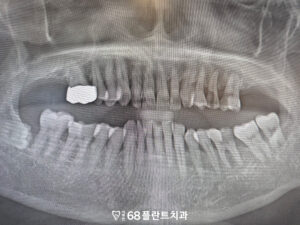

◆ 전 > 후 ◆

치료 마무리 후 사진입니다.

환자분께서는 치료 이후

치아를 전체적으로 쓸 수 있어

매우 만족해 주셨습니다.

또한 살릴 수 있는 치아는 살리면서

정말 치료가 필요한 부분만

발치를 할 수 있어 다행이라며

말씀해 주셨습니다.